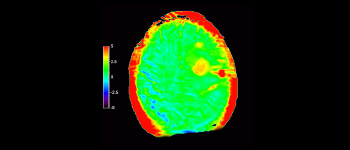

Cerebro con glioblastoma

3D APT

Mayor fiabilidad diagnóstica en neurooncología